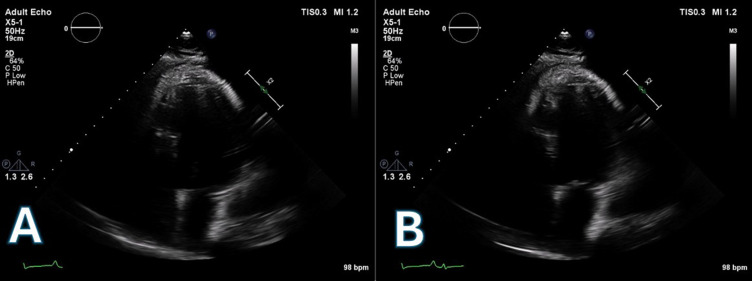

左心室辅助装置(lvad)已成为晚期心力衰竭治疗的重要方式,有时可作为恢复的桥梁。一例30多岁酒精性扩张型心肌病患者在严重心功能不全后行左心室辅助装置植入。6年后,心肌恢复良好,LVAD移植成功。植体术后2年,患者继续存在高危生活方式(如吸烟、饮酒),最终因跌倒并左胸外伤发展为左胸假性动脉瘤。手术修复发现感染,用靶向抗生素治疗。本病例表现出罕见的超声心动图表现,并强调了左心室辅助器移植的复杂性,特别是在患者持续高风险生活方式的情况下。据我们所知,感染的左心室假性动脉瘤并发左心室辅助器移植以前没有报道过。因此,其管理和长期结果无法使用循证指南进行评估。

Left ventricular assist devices (LVADs) have become an important modality of treatment in advanced heart failure, serving sometimes as a bridge to recovery. A subject in his 30s with alcohol-induced dilated cardiomyopathy underwent LVAD implantation following severe cardiac dysfunction. After six years, a sufficient myocardial recovery led to successful LVAD explantation. 2 years post-explant, the patient continued high-risk lifestyle behaviors (like smoking and drinking alcohol) and eventually developed a left thoracic pseudoaneurysm due to a fall with left chest trauma. Surgical repair revealed infection, treated with targeted antibiotics. This case shows a rare echocardiographic presentation and underscores the complexities of LVAD explantation, particularly in patients continuing high-risk lifestyle behaviors. To our knowledge, an infected left ventricular pseudoaneurysm complicating LVAD explantation has not previously been reported. Thus, its management and long-term outcomes could not be assessed using evidence-based guidelines.